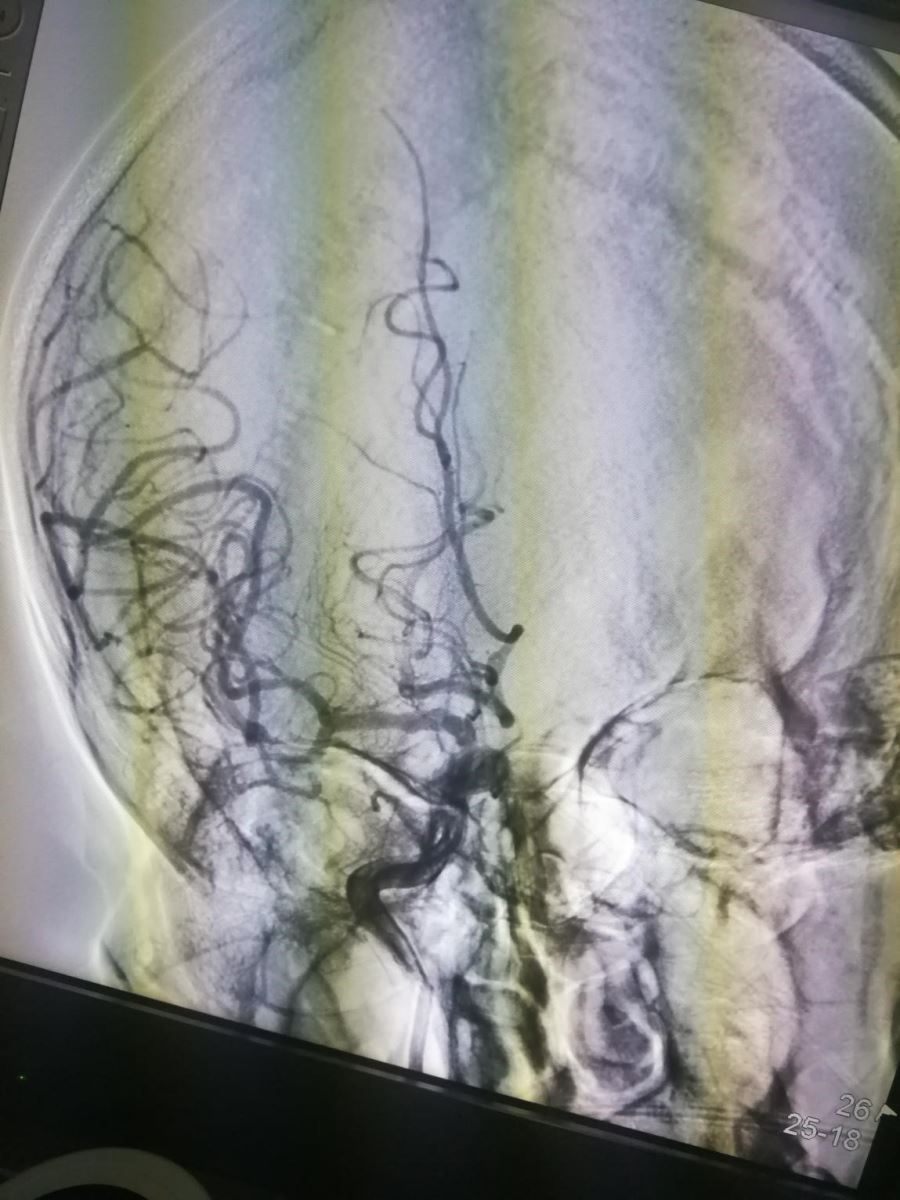

术后再次造影,可见右侧颈总动脉完全通畅(图8、图9)。